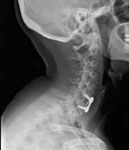

Anterior Cervical Discectomy and Fusion